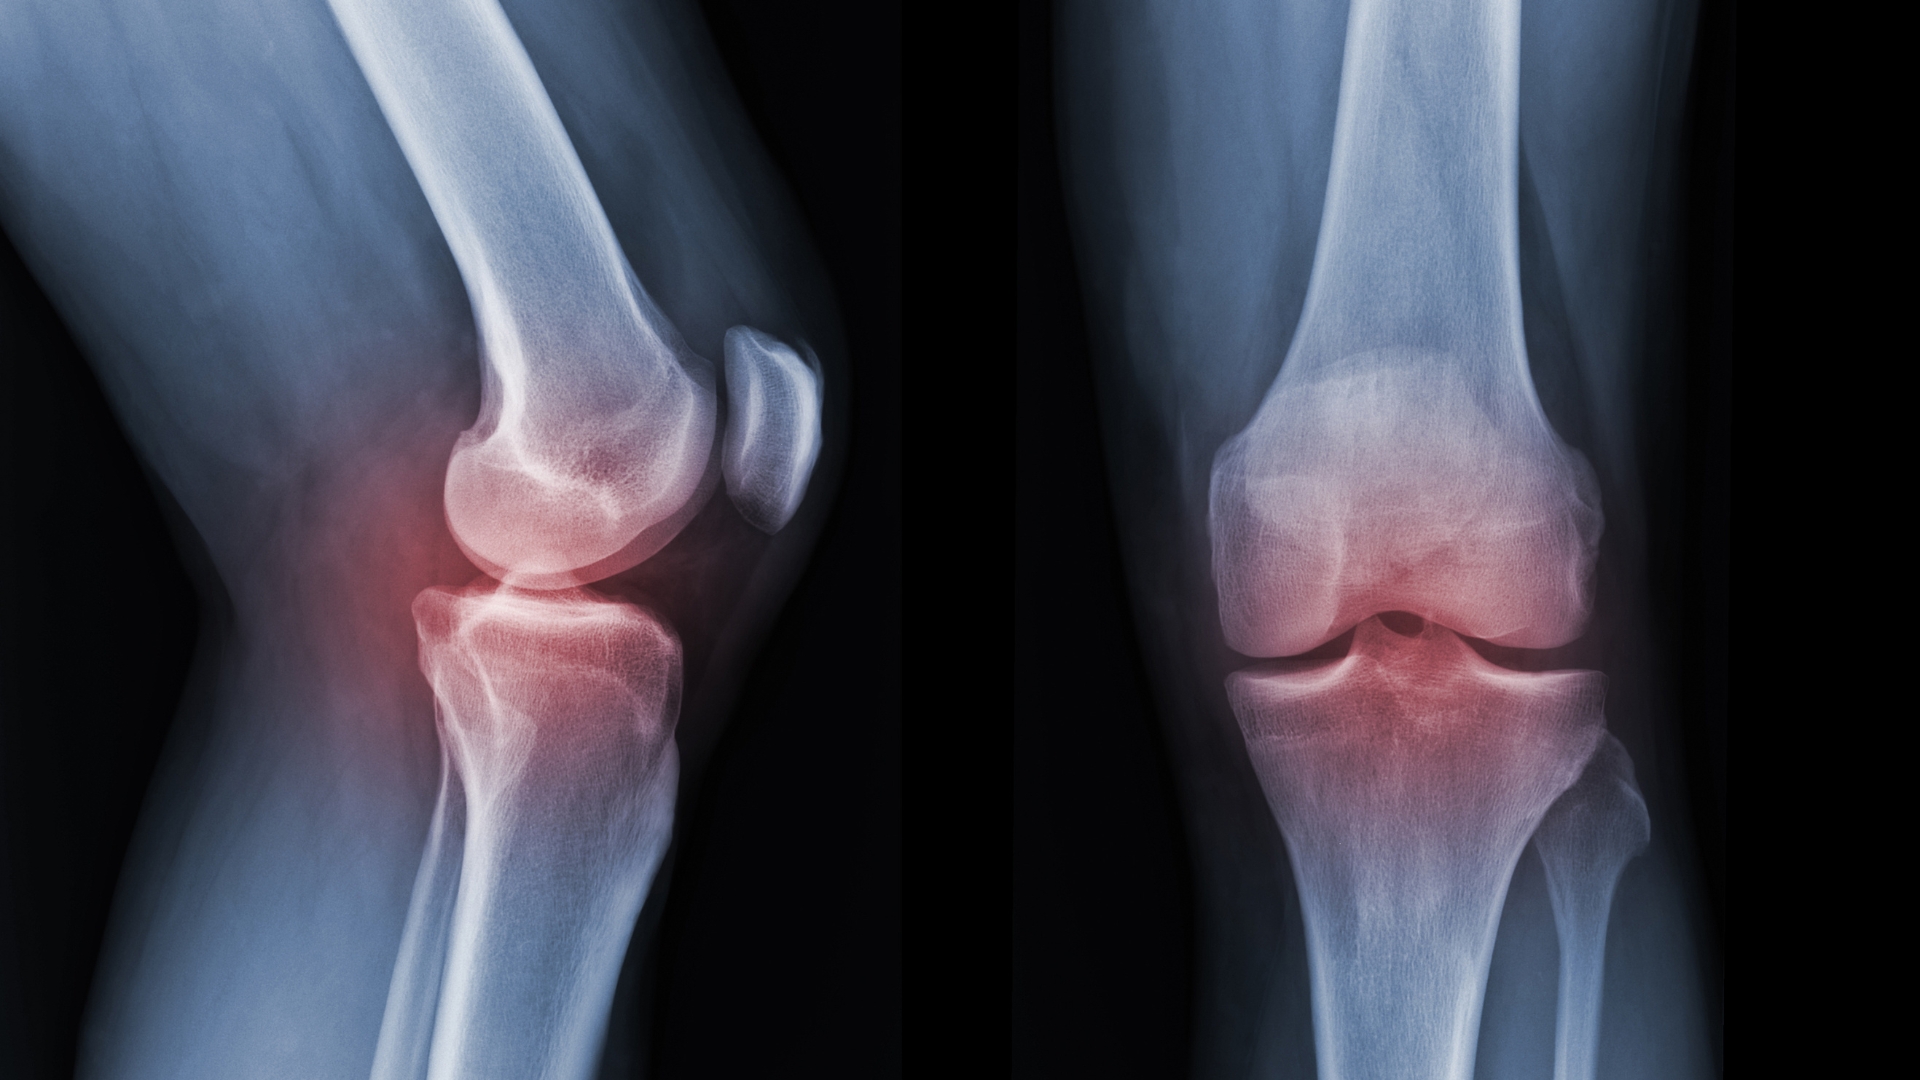

Chụp X-quang khớp gối là phương pháp chẩn đoán hình ảnh sử dụng tia X để ghi lại cấu trúc xương vùng đầu gối dưới dạng hình ảnh hai chiều. Hiện nay, đa số cơ sở y tế áp dụng hệ thống X-quang kỹ thuật số, cho hình ảnh rõ nét và thuận tiện lưu trữ.

Nhờ đó, bác sĩ có thể phát hiện gãy xương, nứt xương, trật khớp hoặc sai lệch trục chi sau chấn thương. Trong các trường hợp thoái hóa, phim X-quang giúp nhận biết dấu hiệu hẹp khe khớp, mọc gai xương hoặc đặc xương dưới sụn.

Tuy nhiên, phương pháp này chủ yếu cho thấy hình ảnh của xương. Các cấu trúc mô mềm như dây chằng, sụn chêm, gân và cơ quanh khớp không được thể hiện rõ trên phim X-quang. Vì vậy, kết quả cần được kết hợp với thăm khám lâm sàng và có thể bổ sung thêm kỹ thuật khác nếu cần để đảm bảo chẩn đoán chính xác.